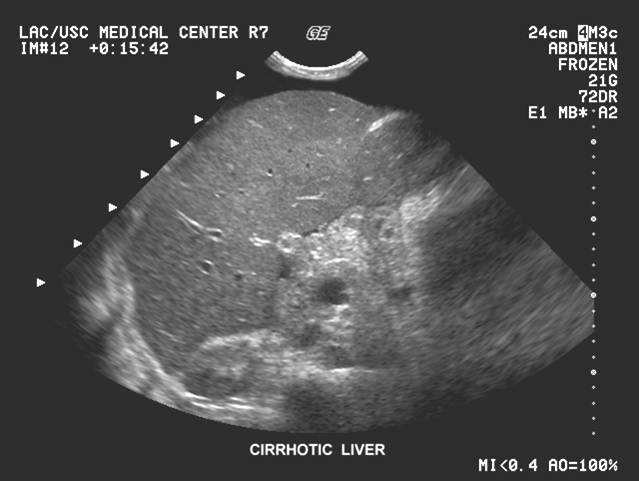

Cirrhosis

parachyma degernerates and lobes infiltate with fat

most common cause ALCHOL

SYM: nauses weight loss flatulence varicosities

SONO

Not advanced: hyperechoic, enlargment, decreased vasculature

ENd stage small noduar, ascites suround